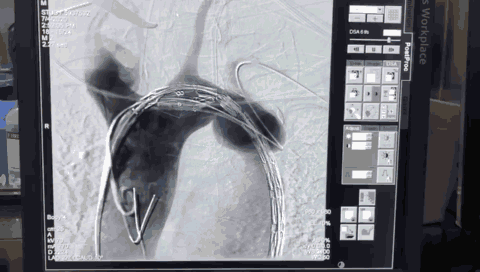

使用球囊28mm*40mm扩张

植入弹簧圈进行填充封堵内漏

“一站式”手术完成